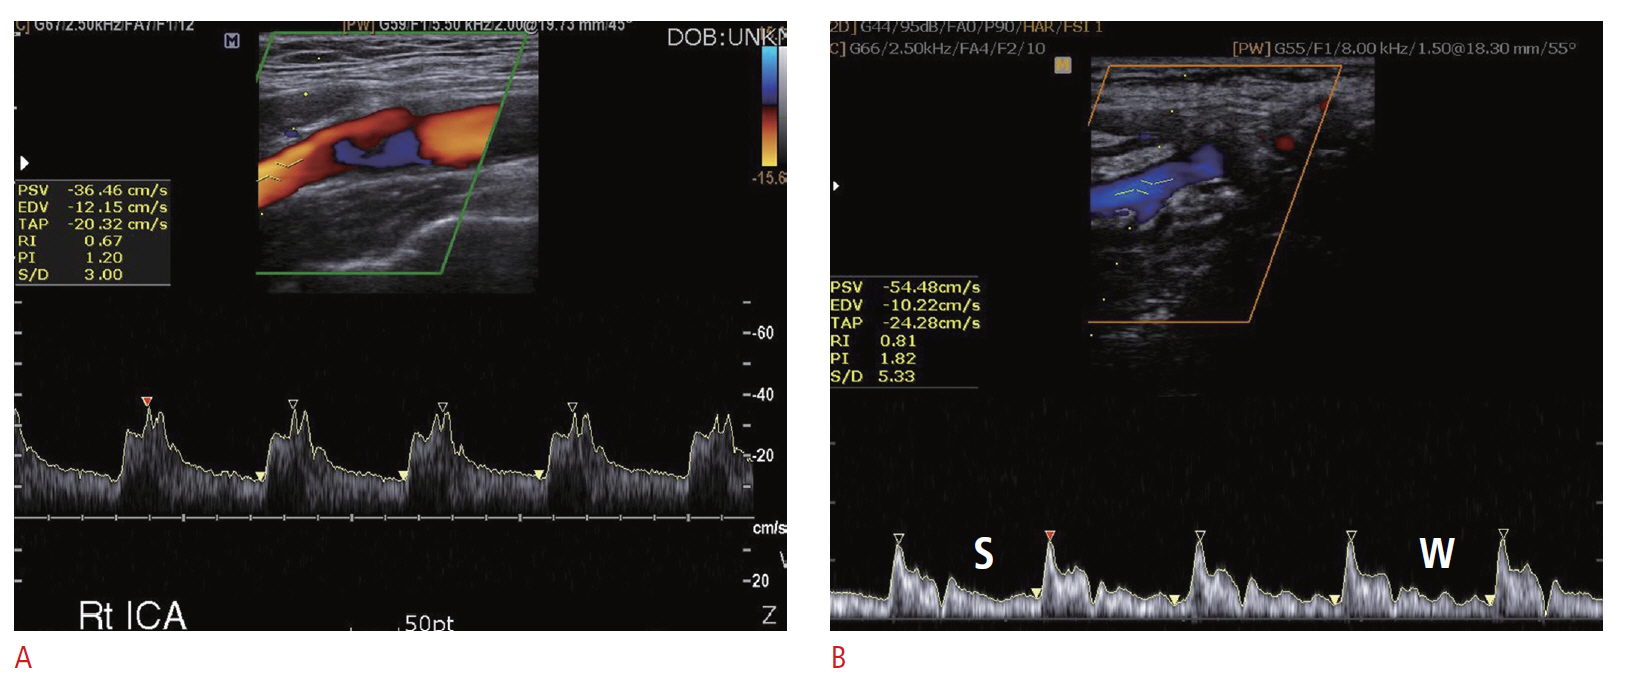

Carotid Doppler ultrasonography is a popular tool for evaluating atherosclerosis of the carotid artery. Its two-dimensional gray scale can be used for measuring the intima-media thickness, which is very good biomarker for atherosclerosis and can aid in plaque characterization. The plaque morphology is related to the risk of stroke. The ulceration of plaque is also known as one of the strong predictors of future embolic event risk. Color Doppler ultrasonography and pulse Doppler ultrasonography have been used for detecting carotid artery stenosis. Doppler ultrasonography has unique physical properties. The operator should be familiar with the physics and other parameters of Doppler ultrasonography to perform optimal Doppler ultrasonography studies.